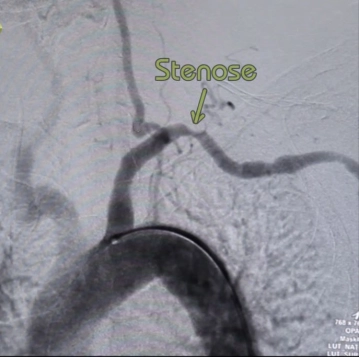

Stenose oder Verschluss der A. subclavia nur bei eindeutig zuordenbarer Symptomatik/Minderperfusion des Armes:

- claudicatio-ähnliche Armbeschwerden (belastungsabhängige Ischämie)

- acrale Läsionen im Bereich der Finger

- Subclavian-Steal-Syndrom